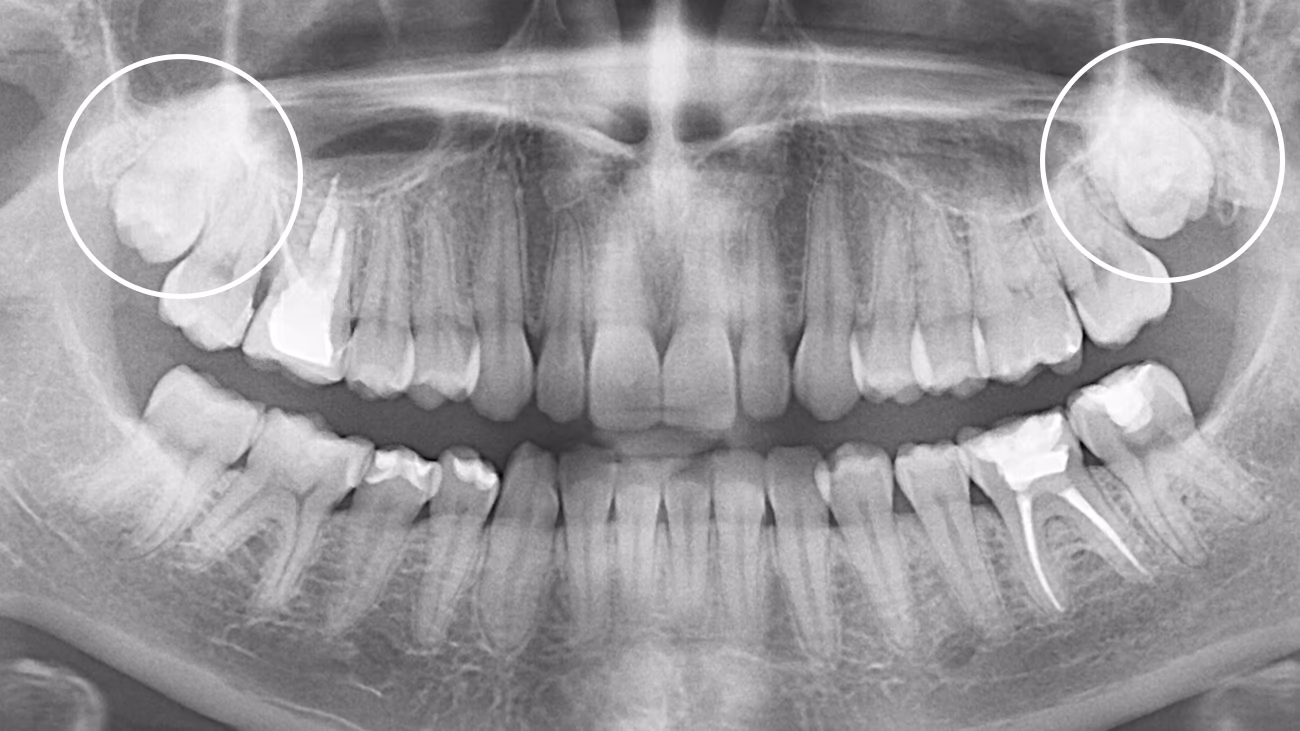

Так. КТ є обов’язковою для точного та безпечного видалення зуба мудрості.

3D-діагностика дозволяє визначити:

• положення зуба

• напрямок росту

• особливості коренів

• близькість до нижньощелепного нерва або верхньощелепної пазухи

У Sergatiy Dental Clinic КТ є обов’язковою перед видаленням зуба мудрості. Без КТ значно підвищуються ризики ускладнень.